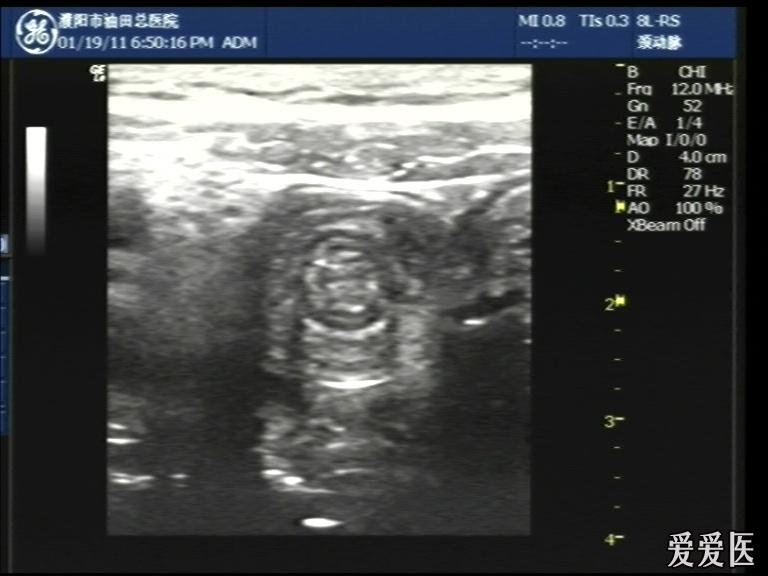

超声检查:于下腹部可见“双环征象”,双环重叠长约6mm,检查期间观察可见肠蠕动;CDFI:未见明显异常血流信号。

超声提示:下腹部双环征,考虑肠套叠可能,请结合临床

“套筒征”、“同心圆征”,很清晰,很经典!

好图,同心圆征。清晰